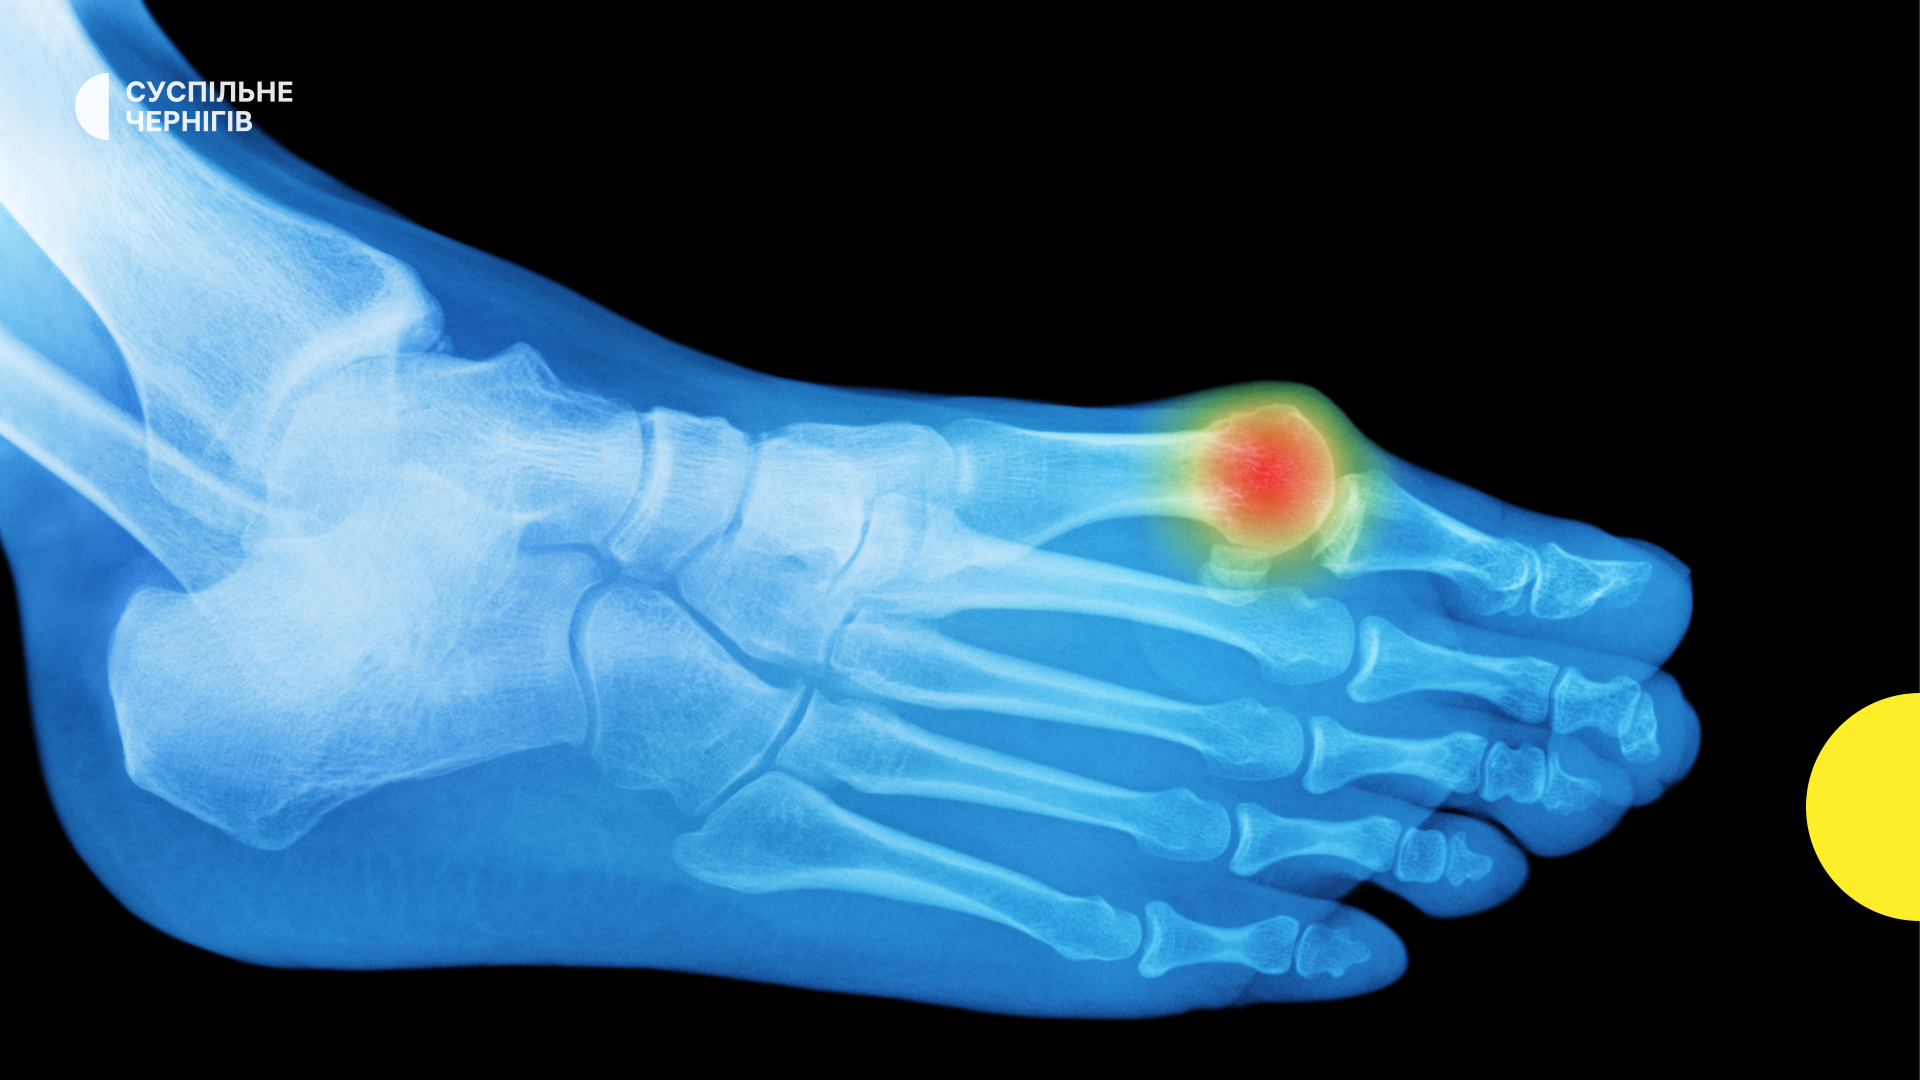

Плюснефаланговом суставе ноги

Плюснефаланговом суставе ноги 114 фото